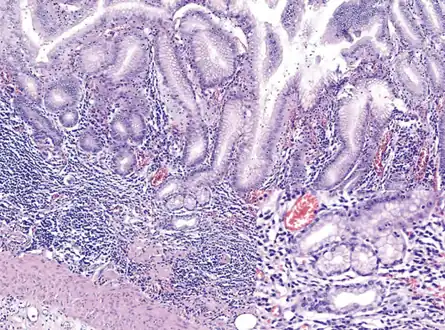

Atrophic gastritis

Atrophic gastritis under low power. H&E stain.

Histopathology of fundic mucosa with atrophy. H&E 10x; square 20x. Fundic-corporal gastric mucosa with extensive loss of gastric glands, partially replaced by pseudo-pyloric metaplasia.